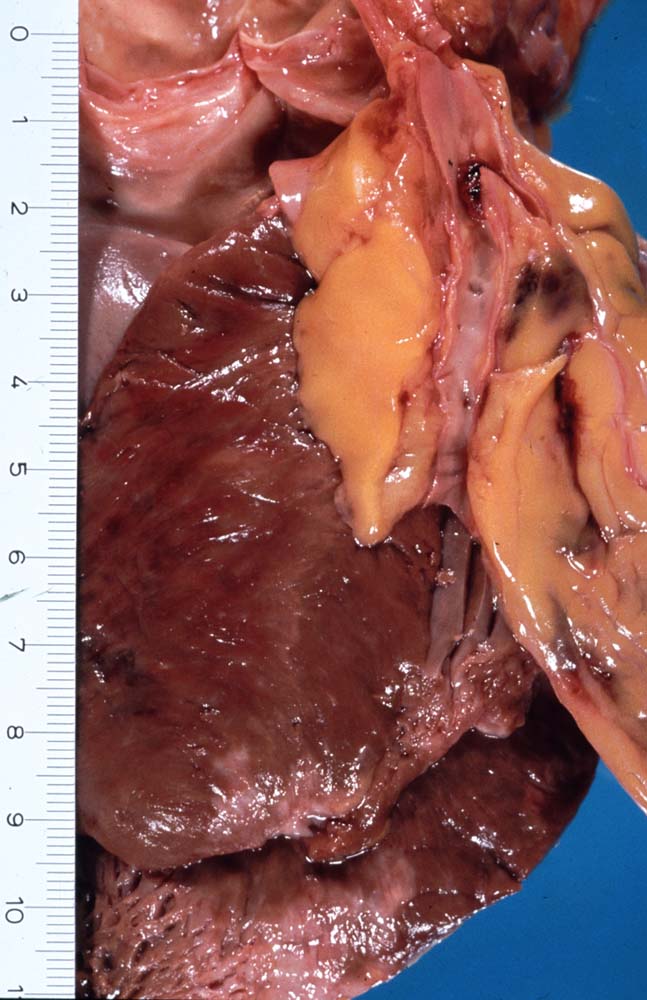

Makroskopisch sind Thromben am besten auf Querschnitten in 3 bis 5mm Abständen durch die Koronargefässe darstellbar. Thromben, die zum Tod des Patienten geführt haben, erkennt man meist makroskopisch. Mikroskopisch findet sich ein Kontinuitätsunterbruch in einer entzündlich veränderten fibrösen Deckplatte über einem Atherom. Dadurch gerät der lipidreiche Kern des Atheroms in Kontakt mit dem luminalen Blutstrom und dies führt zur Ausbildung eines Plättchen-Fibrin Thrombus und zur Einblutung in das Atherom. Meist zeigt der Thrombus Zeichen der beginnenden Organisation. Histologisch ist bei einer Ruptur die denudierte Endotheloberfläche von einem luminalen Thrombus bedeckt.

• Atherom mit fibröser Deckplatte.

• Exzentrische Lumeneinengung durch Verdickung der Intima.

• Organisierender geschichteter Abscheidungsthrombus über Defekt in der fibrösen Deckplatte. Der Thrombus enthält zusätzlich Atherombestandteile (Cholesterinkristalle und nekrotischer Detritus).